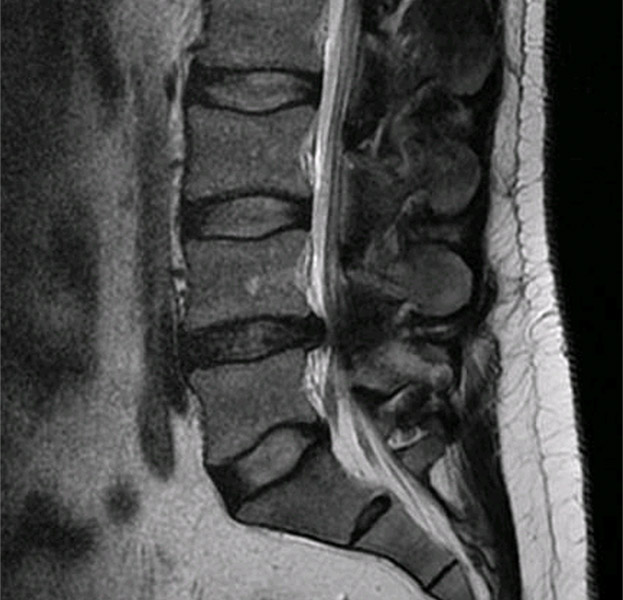

Resonancia con hernia discal

Resonancia con hernia discal L4l5 corte axial

Estos dolores están provocado por una compresión del nervio a la altura de la L4L5.